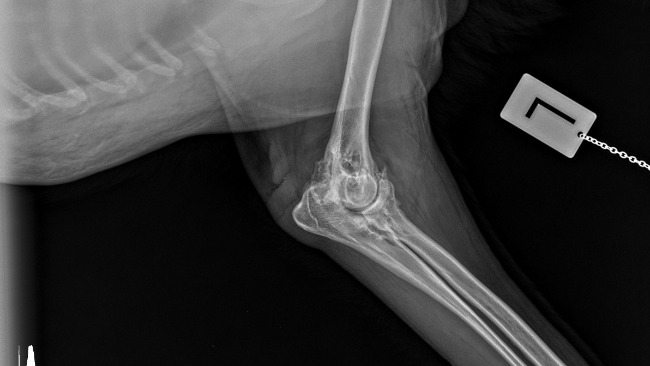

Nóżka Kokoszka, choć nadal obrzęknięta, dobrze się goi i nasz dzielny psiak stawia na niej swoje wielkie łapeczki.

Fot. Droga chłopaków do równowagi psychicznej. Wizyty w gabinecie lek.wet.

Małgorzata Płoskonka